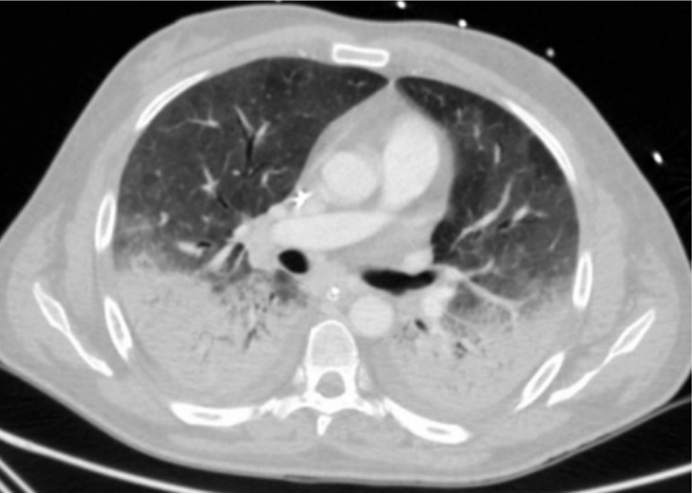

实际案例中,我们看到这一例ARDS患者,早期呈病毒性肺炎的磨玻璃样改变(图7),随着病情进展,11小时后氧合下降,胸部CT可见渗出增加、肺实变,予以气管插管,呼吸机辅助(图8);呼吸机支持2天后,胸部CT示实变进一步加重,呈现ARDS典型的“重力依赖”CT表现(图8)。这种情况可能就是呼吸机参数设置不当,加重了肺损伤。

图片

图7  患者入院早期胸部CT

图8  11小时后和2天后胸部CT